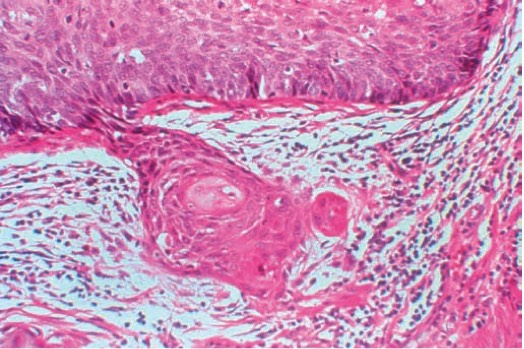

1022. Изменениям, обнаруженным у 33-летней женщины при биопсии шейки матки, наиболее подходит диагноз